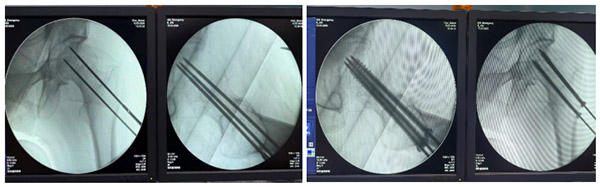

3月13日,手术顺利开展。在骨外科手术机器人导航系统支持下,团队通过术中影像完成骨折部位图像采集,精准规划螺钉置入角度与深度;机械臂实时引导、定位,实现亚毫米级精准操作,仅通过微小切口即完成骨折闭合复位与螺钉内固定。

◆定位更准:螺钉位置误差控制在毫米级,有效避开血管、神经;

◆辐射更低:减少术中反复透视,降低医患双方辐射暴露;